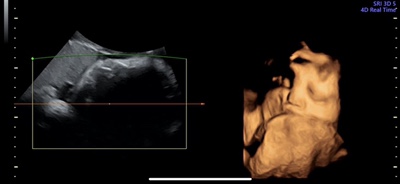

출산전 마지막 검사 36주 6일

#임산부막달검사 #막달검사 25일 일요일 제왕 수술 날짜 잡혔고..^^.. 출산 전 마지막 검사와 마지막 초음...

33주 2일 셋째 임신 ㅊ기록

#33주2일 #임산부 #셋째맘 #다둥맘 여전히 얼굴은 안 보여주는 동동쓰 코가 크고 오똑하다고 칭찬해주셨다 ...